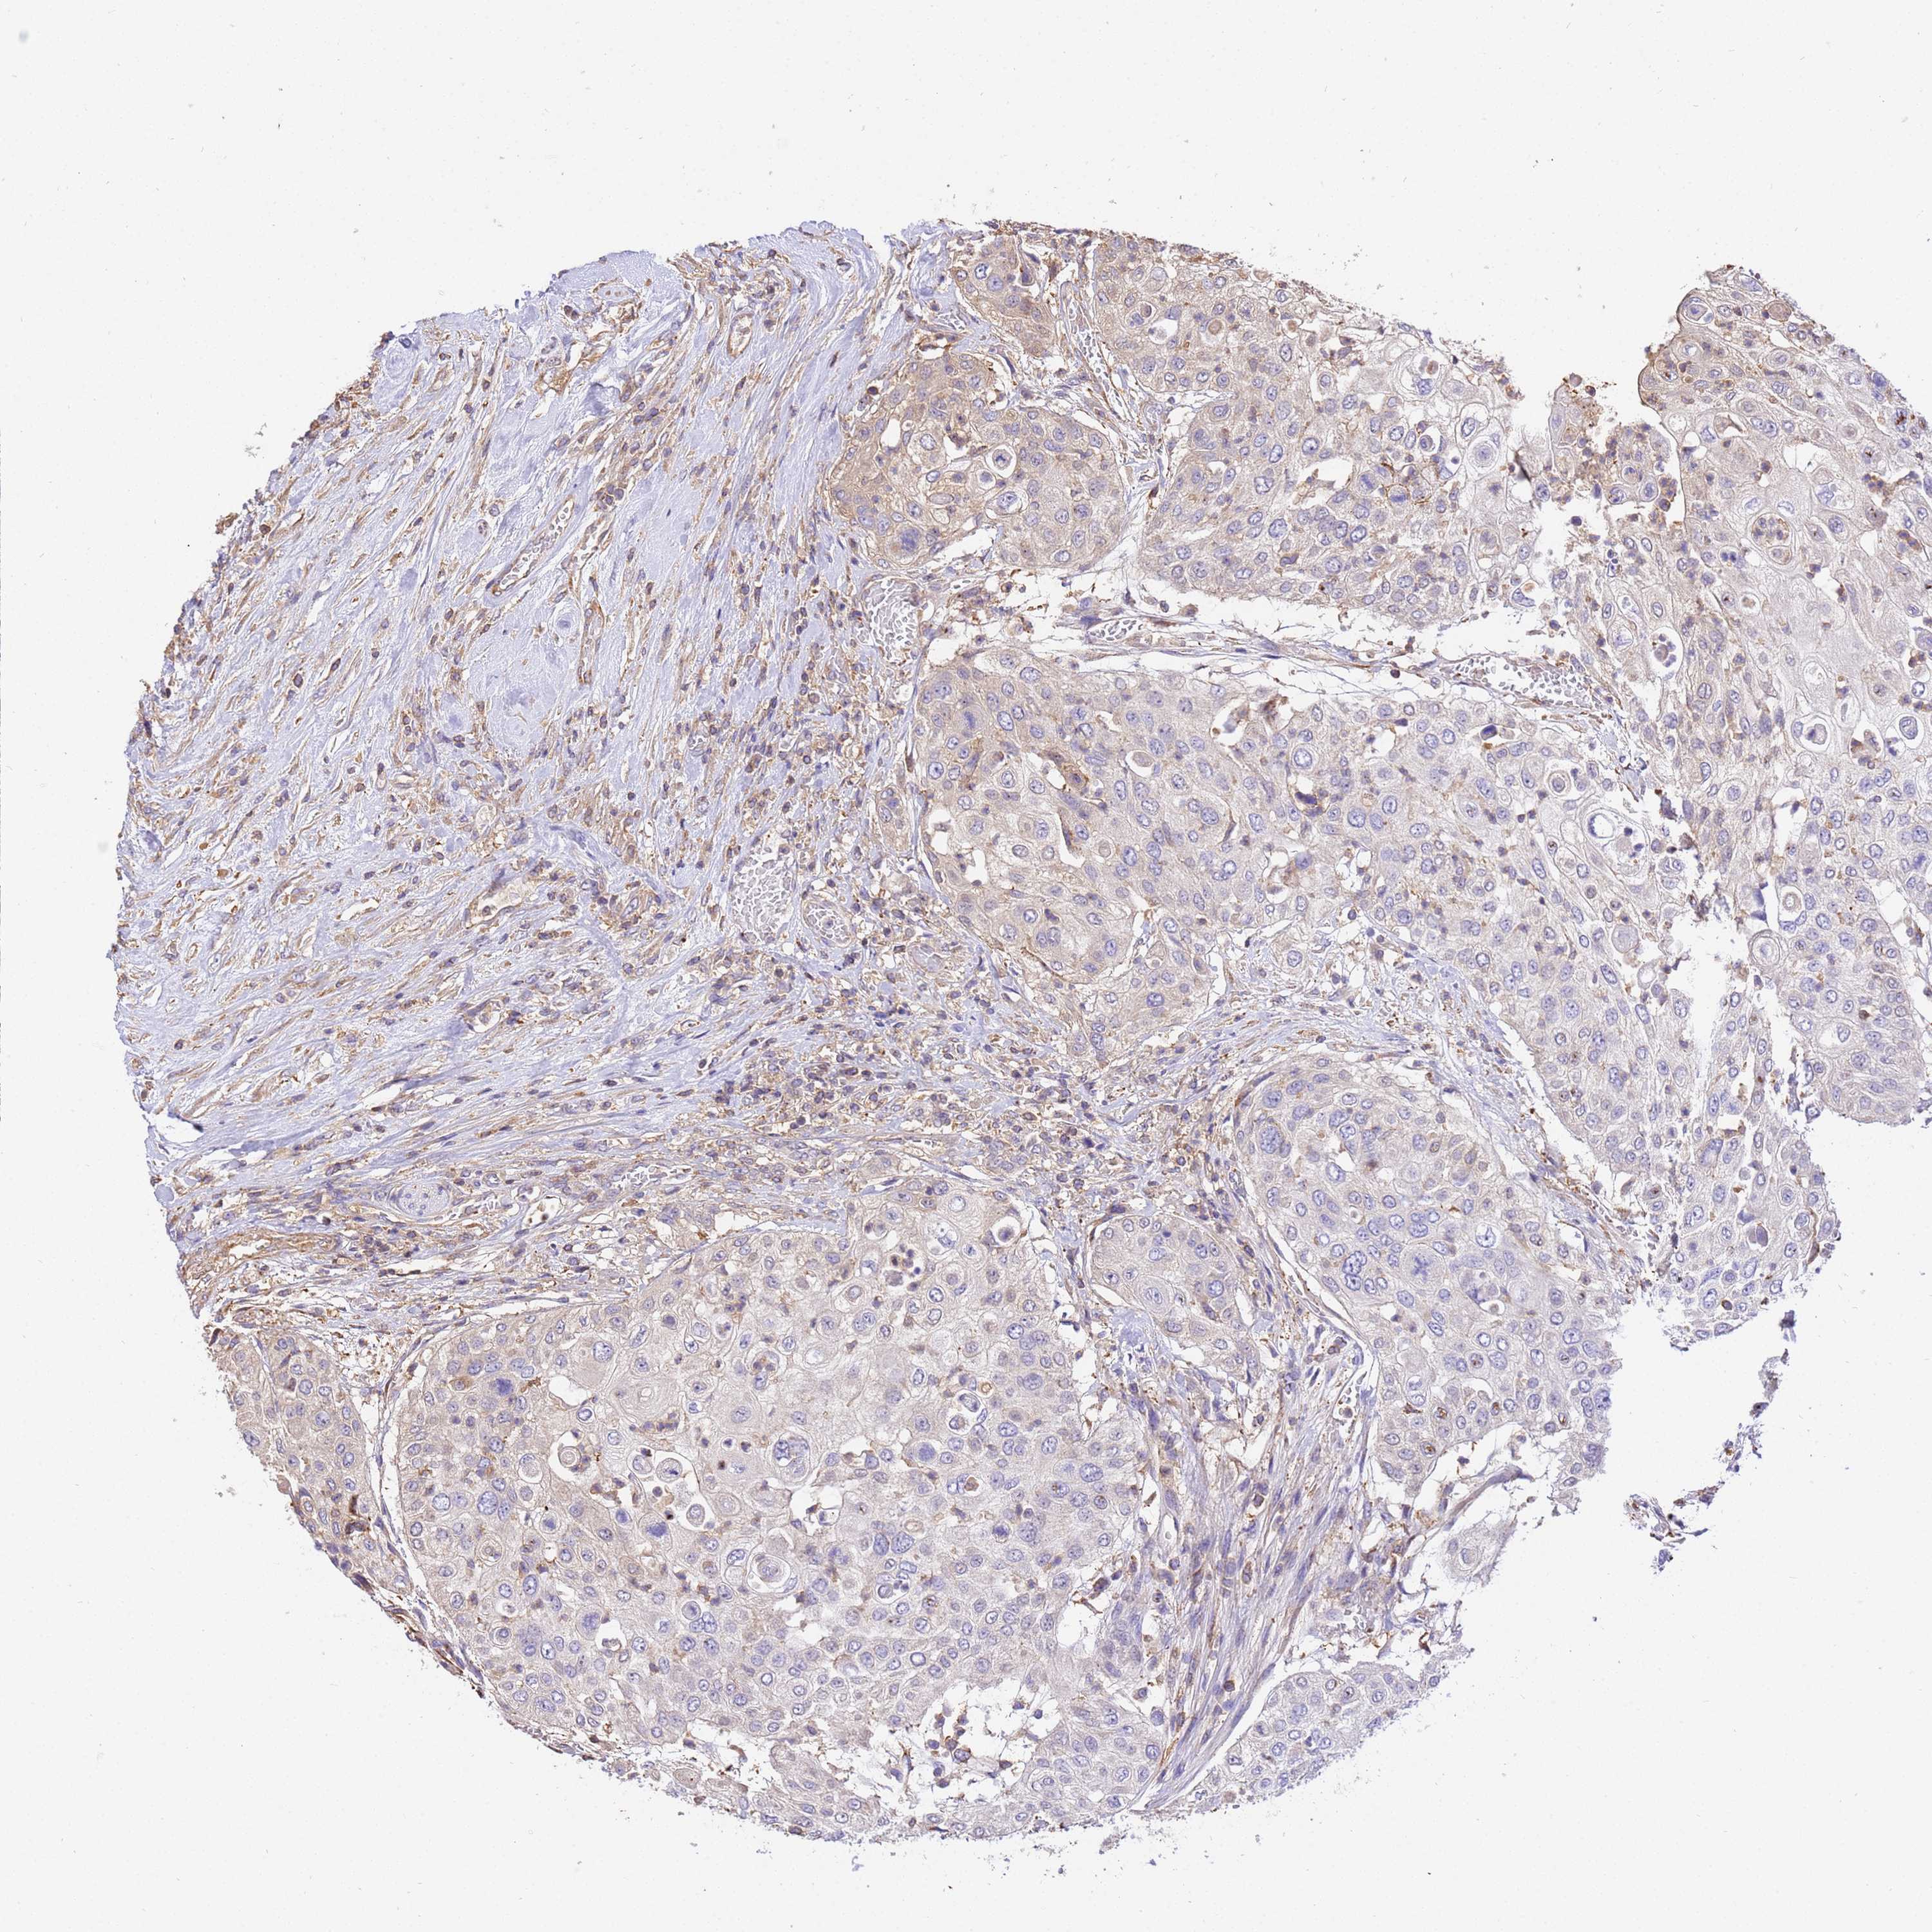

UROTHELIAL CANCER - Protein expressioni

A mouse-over function shows sample information and annotation data. Click on an image to view it in a full screen mode. Samples can be filtered based on level of antibody staining by selecting one or several of the following categories: high, medium, low and not detected. The assay and annotation is described here.

Note that samples used for immunohistochemistry by the Human Protein Atlas do not correspond to samples in the TCGA dataset.

Antibody stainingi

Antibody staining in the annotated cell types in the current human tissue is reported as not detected, low, medium, or high, based on conventional immunohistochemistry profiling in selected tissues. This score is based on the combination of the staining intensity and fraction of stained cells.

Each image is clickable and will lead to virtual microscopy that enables deeper exploration of all samples and also displays staining intensity scores, fraction scores and subcellular localization as well as patient and tissue information for each sample.

Antibody HPA046186

Staining

High

Medium

Low

Not detected

Intensity

Strong

Moderate

Weak

Negative

Quantity

>75%

75%-25%

<25%

None

Location

Nuclear

Cytoplasmic/membranous

Cytoplasmic/membranous,nuclear

Urothelial carcinoma, High grade